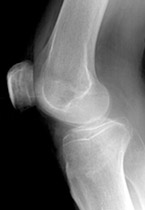

Lateral Tibial Plateau Fracture

• When depression is not present, fracture may be difficult to recognize with standard radiographic exam. Alternative views and/or CT may be required for diagnosis.

• CT with multiplanar reconstruction (MPR) can be useful to help understand the anatomy of the fracture in 3D.

• Postraumatic arthritis and malunion can result.